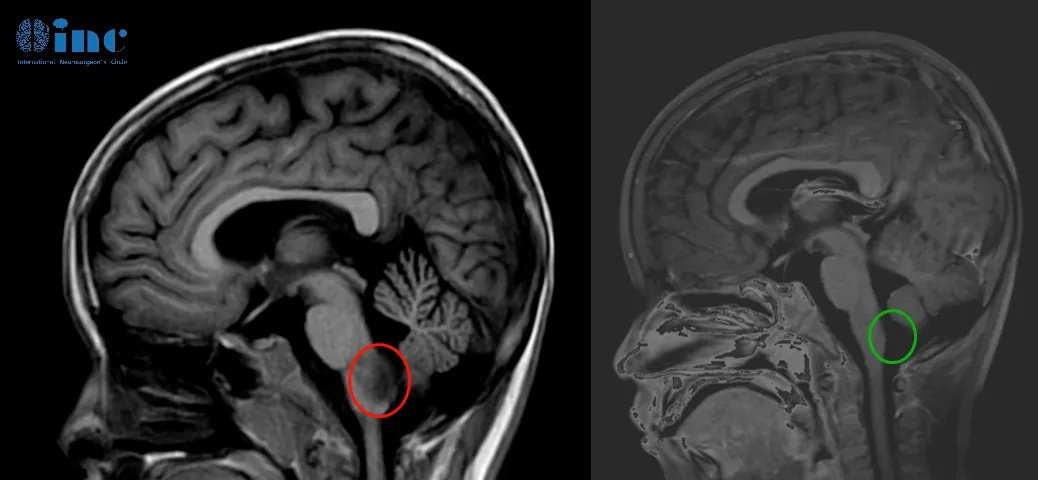

▼天天术前术后影像对比

巴教授近全切天天的脑干-延髓毛细胞星形细胞瘤。

术后第三天查房交流清晰、肢体抓握能力正常、术后呼吸吞咽正常,食欲正常,已经可以正常吃饭进食。